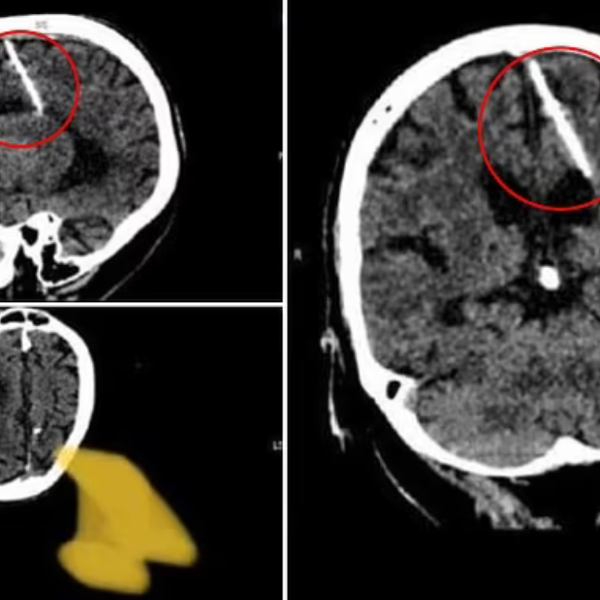

Por medio de una tomografía computarizada, una mujer rusa de 80 años descubrió que ha tenido una aguja de tres centímetros enterrada en su cerebro desde que era bebé.

Los doctores encontraron el objeto cuando la anciana acudió al hospital de Sakhalin, una isla al norte de Japón, para realizar unas revisiones médicas no especificadas. Puesto que nunca experimentó síntomas por el elemento introducido en cuestión, los galenos prefirieron abstenerse de extraerlo por medio de una cirugía.

El departamento de salud de Sakhalin detalló en la aplicación de mensajería Telegram que "la aguja penetró en su lóbulo parietal izquierdo, pero no tuvo el efecto deseado, la niña sobrevivió (...) La salud del paciente no está en peligro; su estado está siendo supervisado por el médico tratante”.

El caso médico se volvió viral por las imágenes compartidas de las tomografías en las que se puede observar la fina varilla metálica entre el cerebro de la paciente. Tras aproximadamente ocho décadas en las que la anciana ha vivido con el objeto sin experimentar un malestar que devenga de este, los expertos pronostican que no enfrentará complicaciones en el futuro.